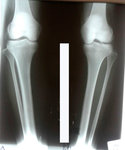

Исходник - 24 года.

2-я ротация.

Дата операции 19.07.2017г.